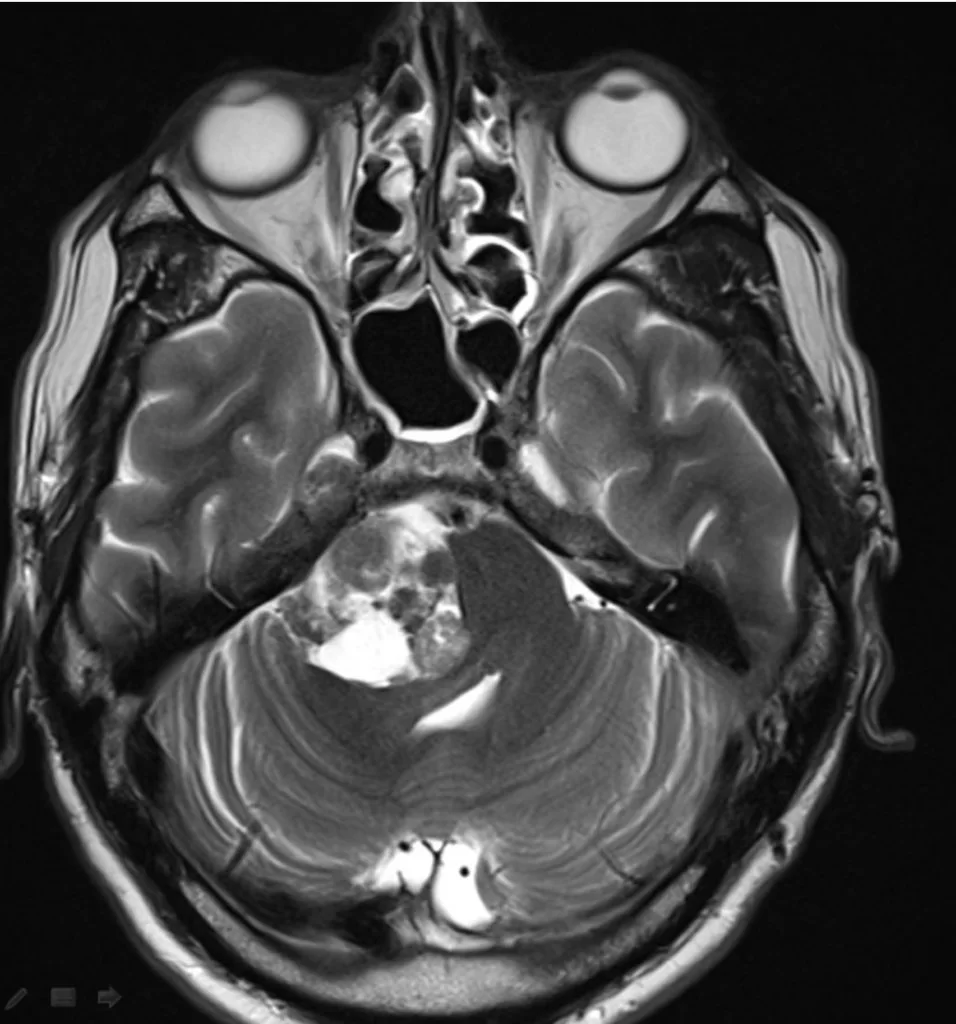

Η μαγνητική τομογραφία εγκεφάλου ανέδειξε εκτεταμένη χωροκατακτητική εξεργασία στην γεφυροπαρεγκεφαλιδική γωνία δεξιά, με επέκταση στην περιοχή του γασσέρειου γαγγλίου του τριδύμου .

Διενεργήθη δεξιά οπισθοσιγμοειδική κρανιοτομία με drilling της κορυφής του λιθοειδούς (suprameatal apicectomy)

Η μετεγχειρητική μαγνητική τομογραφία εγκεφάλου δείχνει ένα εξαιρετικό αποτέλεσμα, με πλήρη αφαίρεση της βλάβης. Η ιστολογική ανέδειξε μηνιγγίωμα WHO I.

Κάθε όγκος της γεφυροπαρεγκεφαλιδικής γωνίας έχει τις ιδιαιτερότητές του και απαιτεί άριστη γνώση της ανατομίας της περιοχής και λεπτούς χειρισμούς. Στην προκειμένη περίπτωση, προβληματική είναι η επέκταση της βλάβης στην περιοχή του γασσέρειου γαγγλίου (Cavum Meckeli). Προκειμένω να επιτύχουμε ολική εξαίρεση εφαρμόσαμε μια πολύ ιδιαίτερη τεχνική και συγκεκριμένα τη μείωση (drilling) της κορυφής του λιθοειδούς από μια οπισθοσιγμοειδική προσπέλαση (suprameatal apicectomy).